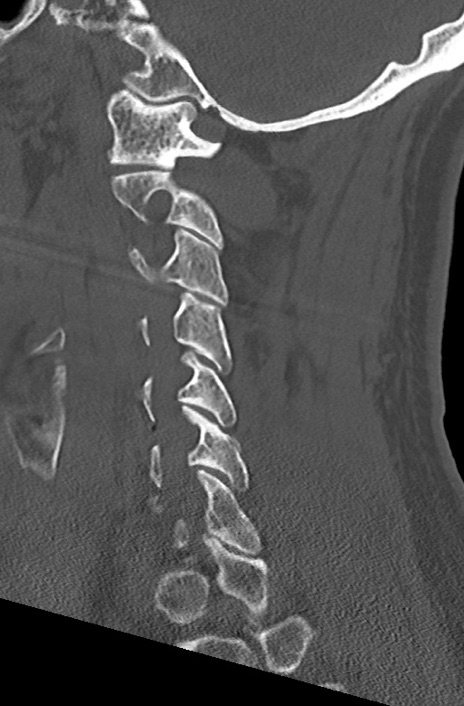

頚椎CT

矢状断像と横断像